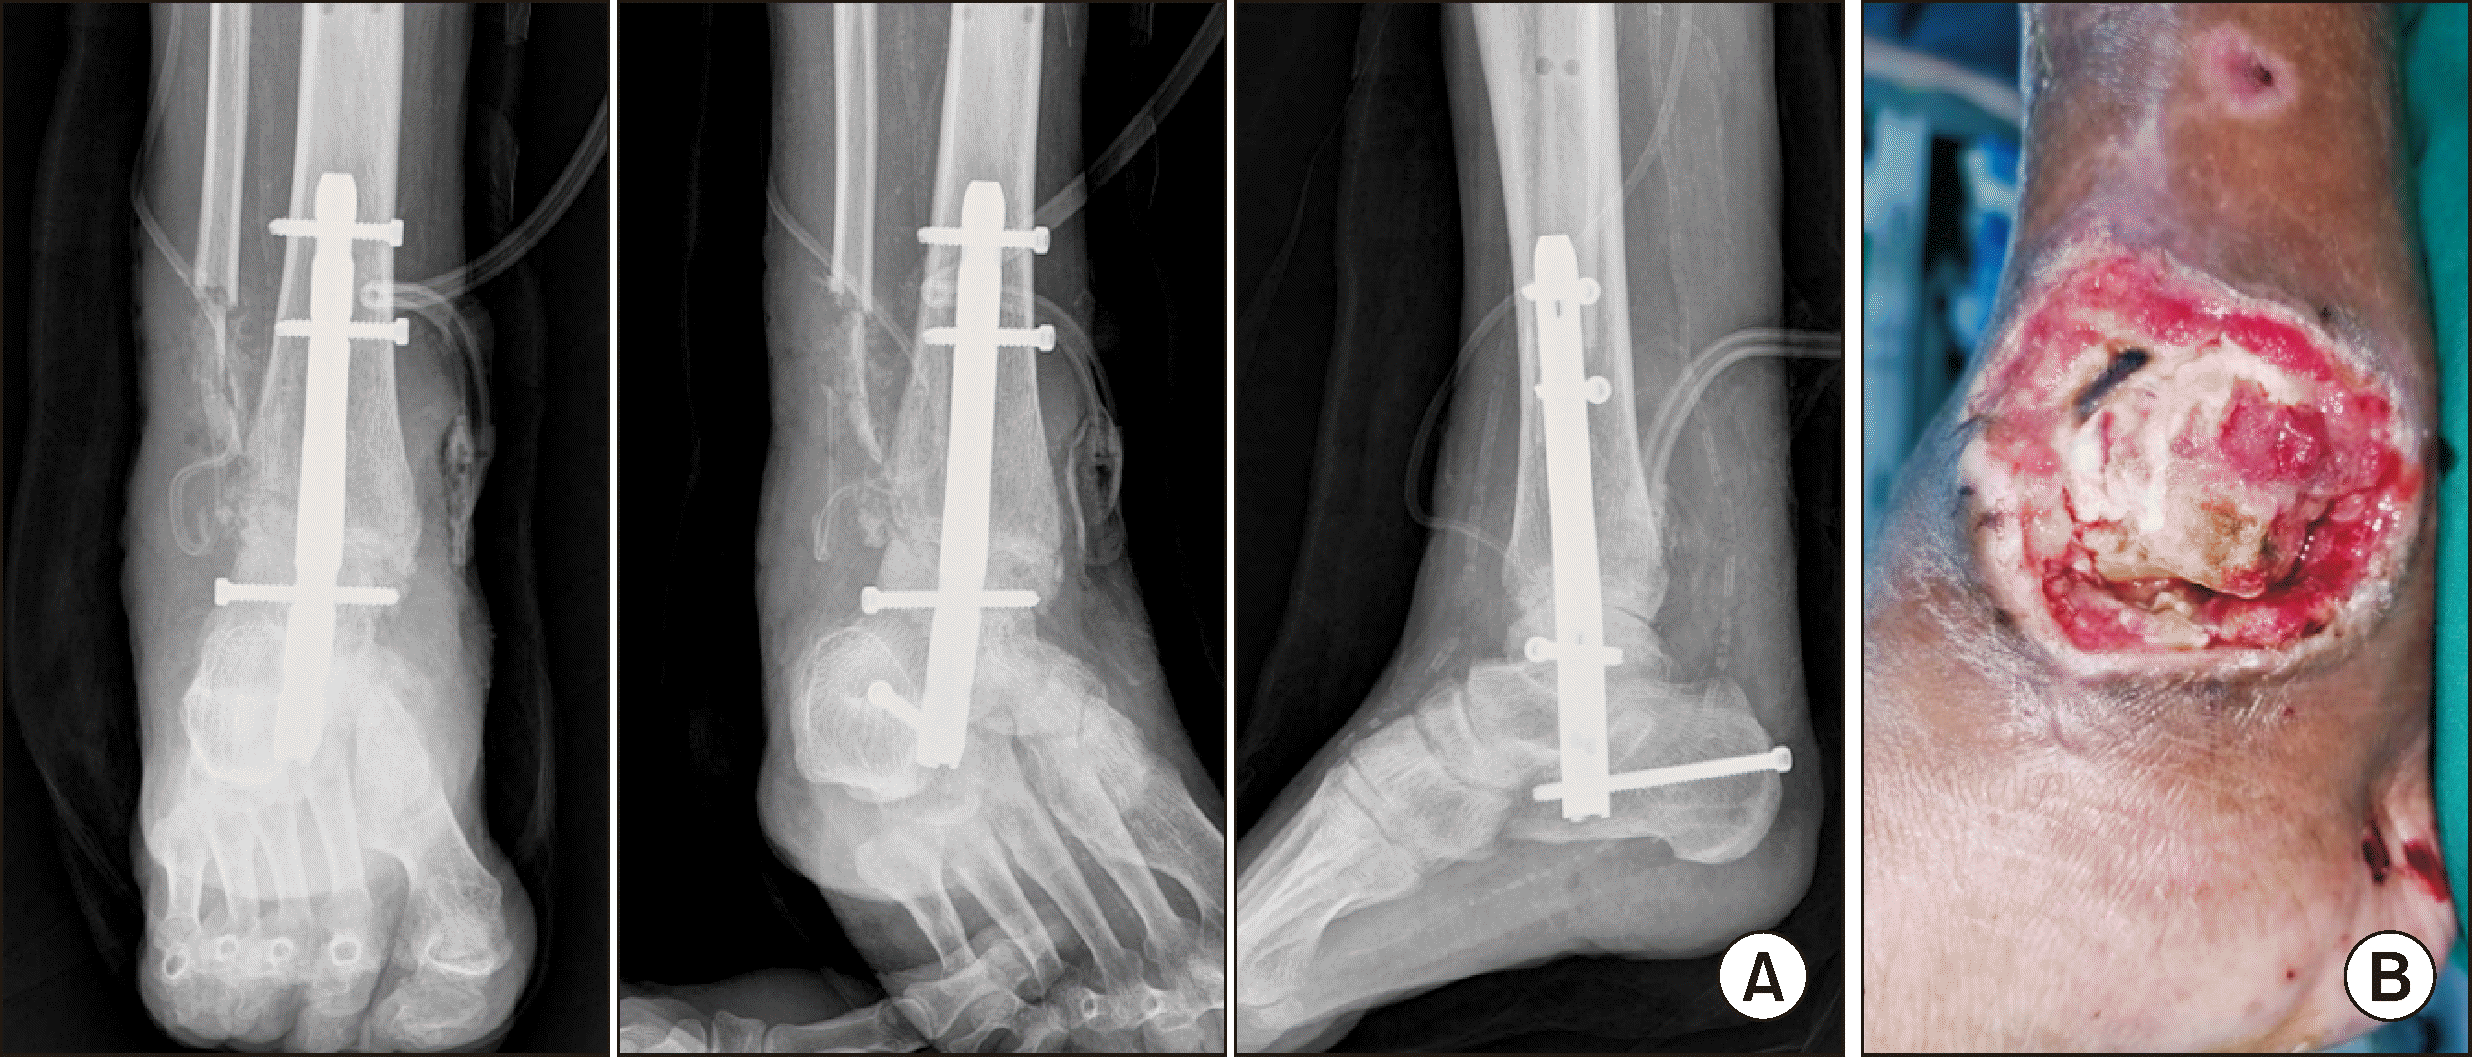

The patient experienced a traumatic right ankle trimalleolar fracture following a slip on an icy surface (Fig. 1). Initial surgical intervention including open reduction and internal fixation (OR/IF) was planned. However, this was postponed due to unforeseen clinical manifestations: the patient developed a high fever of 38°C and elevated C-reactive protein (CRP) levels at 170.2 mg/L (normal range: 0.0∼5.0 mg/L), suggesting systemic inflammation or infection. Moreover, a hemorrhagic bulla rapidly emerged at the site of the medial malleolus deteriorating progressively (Fig. 2).

After the stabilization of the acute symptoms, the patient underwent OR/IF. A plate and screws were utilized for the lateral malleolus and K-wires were employed for the medial malleolus. In addition, syndesmotic fixation was performed to stabilize the distal tibiofibular joint (Fig. 3). In this case, K-wire was used for syndesmotic fixation due to the poor soft tissue condition observed around the medial malleolus. While screw fixation or suture anchor may provide stronger stability, the less invasive nature of K-wire was prioritized to minimize additional injury. Additionally, given the risk of poor bone quality we sought to avoid hardware failure or excessive stress. Upon observing a reduction in post-operative swelling, a short leg cast was applied (Fig. 4).

Figure 1

(A) Initial radiograph imaging upon admission showing a right ankle trimalleolar fracture. (B) Initial clinical picture upon admission showing a right ankle trimalleolar fracture.

Figure 4

Post-cast radiograph following the application of a short leg cast after the reduction of swelling.

Figure 5

(A) Five weeks post-surgery, radiograph confirming non-union and lateral displacement of the fractures. (B) Findings of metal failure and tibiotalar joint dislocation observed during COVID-19 isolation.